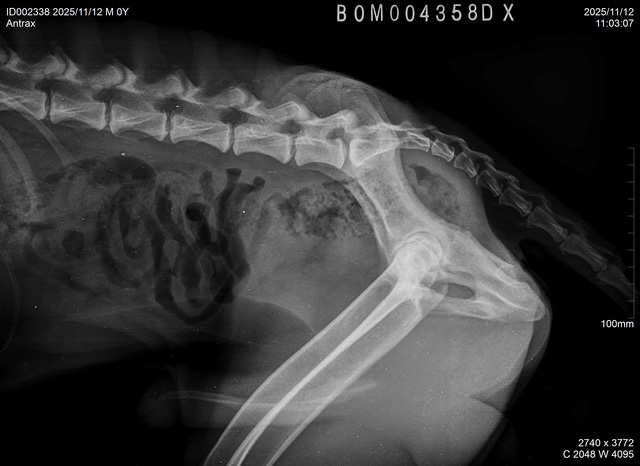

| ANTRAX, DOB July 2 2024, elbows/hips/spine: see x-rays below. ATRAX is almost 2 years old malinois male that was raised in the kennel. He is used to stay both inside the kennel as well as inside of house. He is good with other dogs and has no problem with other animals. ATRAX is a normal social dog and he gets used to the new handler and environment quickly. ANTRAX doesn't have problem with any kind of surface. ANTRAX has excellent ball drive. He is able to search for hidden ball in very hard environments and conditions. He searches with great interest and persistance until he finds the ball. His protection is also excellent. He has fast and hard bites. He is able to work inside and outside of buildings and he can bite on sleeve as well as bite suit. ANTRAX is suitable as a dog for personal protection or as a dual purpose law enforcement dog. |

X-RAYS: